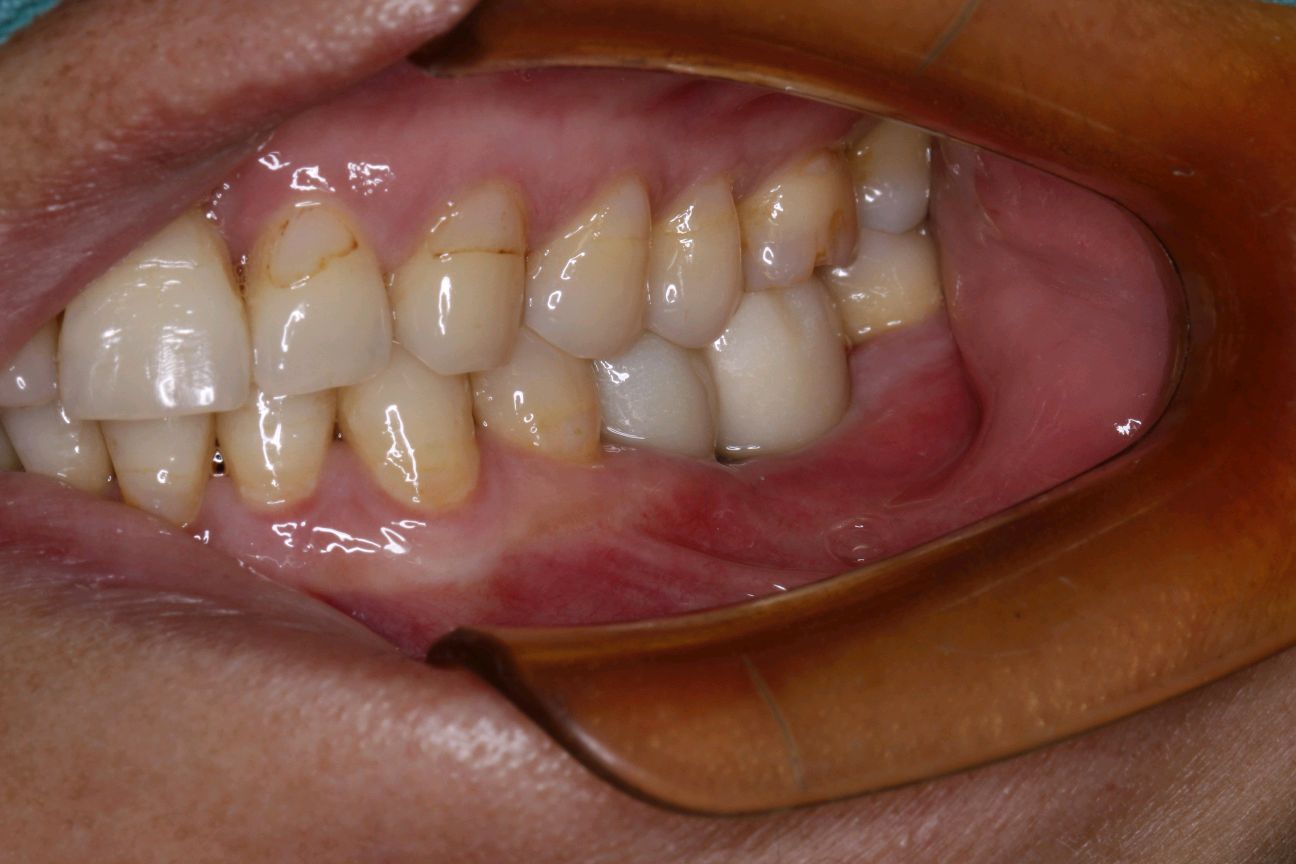

患者女,49岁,全口口腔卫生不良,结石++,牙槽骨水平吸收,附着丧失,可探及牙周袋。35,36,牙周-牙髓联合病变导致牙齿松动+++,根尖周阴影呈“烧瓶形”病变。

最终患者在做完牙周治疗后,拔除患牙。三月后植入ITI种植系统,植入骨粉骨膜及CGF膜严密缝合。术后骨结合良好。二期三期如期顺利进行,最终于今日安装牙冠,完成种植。患者满意。